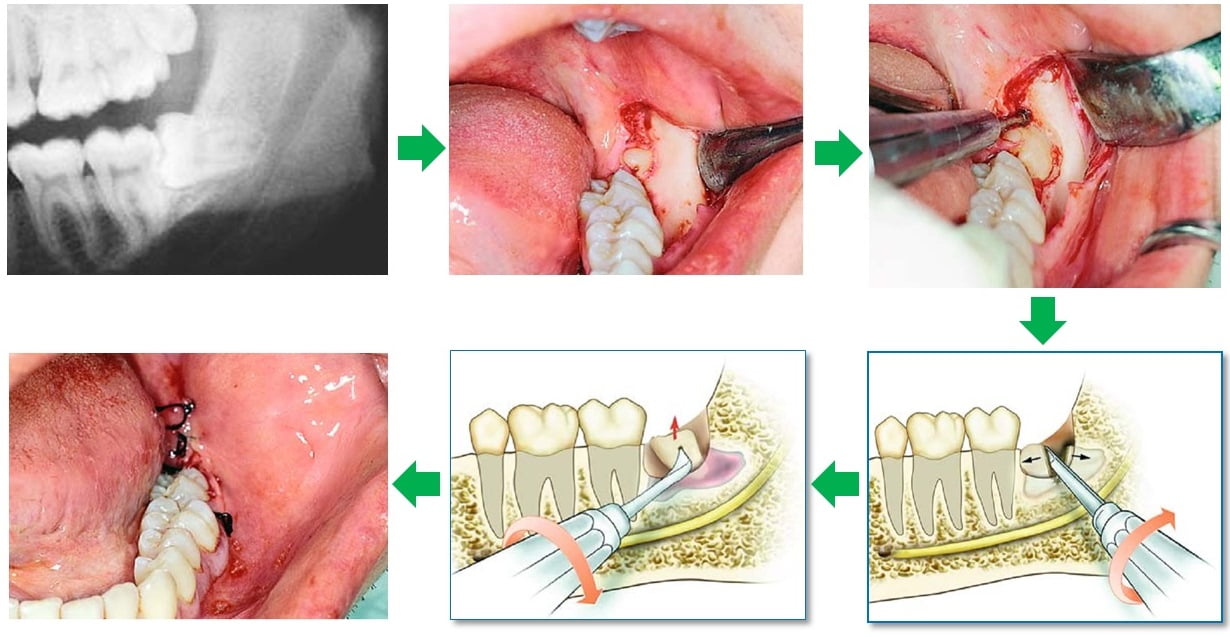

Quy trình nhổ răng khôn

Thực hiện tiểu phẫu

– Bệnh nhân súc miệng bằng nước súc miệng chuyên dụng, sau đó được sát khuẩn vùng răng cần nhổ

– Bác sĩ gây tê vùng cần nhổ răng

– Bác sĩ thực hiện phẫu thuật (tùy theo tình trạng răng cần nhổ mà bác sĩ sẽ có các can thiệp sâu hơn trước khi nhổ)

– Bệnh nhân cắn chặt bông để cầm máu, kết thúc ca tiểu phẫu.

Quy trình nhổ răng số 6

– Thăm khám tổng quan và chụp x-quang răng

Xác định tình trạng răng sâu , vị trí chính xác và lên phương án nhổ răng an toàn, hợp lý.

– Gây tê tại chỗ

Loại thuốc tê sẽ có tác dụng trong vòng khoảng 2 h đồng hồ. Sau thời gian hết thuốc gây tê, có thể bạn sẽ cảm thấy hơi đau nhức một chút. Tuy nhiên, với tác dụng của thuốc giảm đau thì cơn đau cũng không kéo dài.

– Bắt đầu tiến hành nhổ răng

Đây là công đoạn đòi hỏi kỹ thuật nhiều nhất của nha sĩ. Công nghệ nhổ răng hiện đại hạn chế được việc chảy máu khá tốt. Thay vì dùng kìm nhổ răng như trước đây, giải pháp đưa ra là cắt các kết nối răng thành các mảnh nhỏ rồi gắp ra nhẹ nhàng.